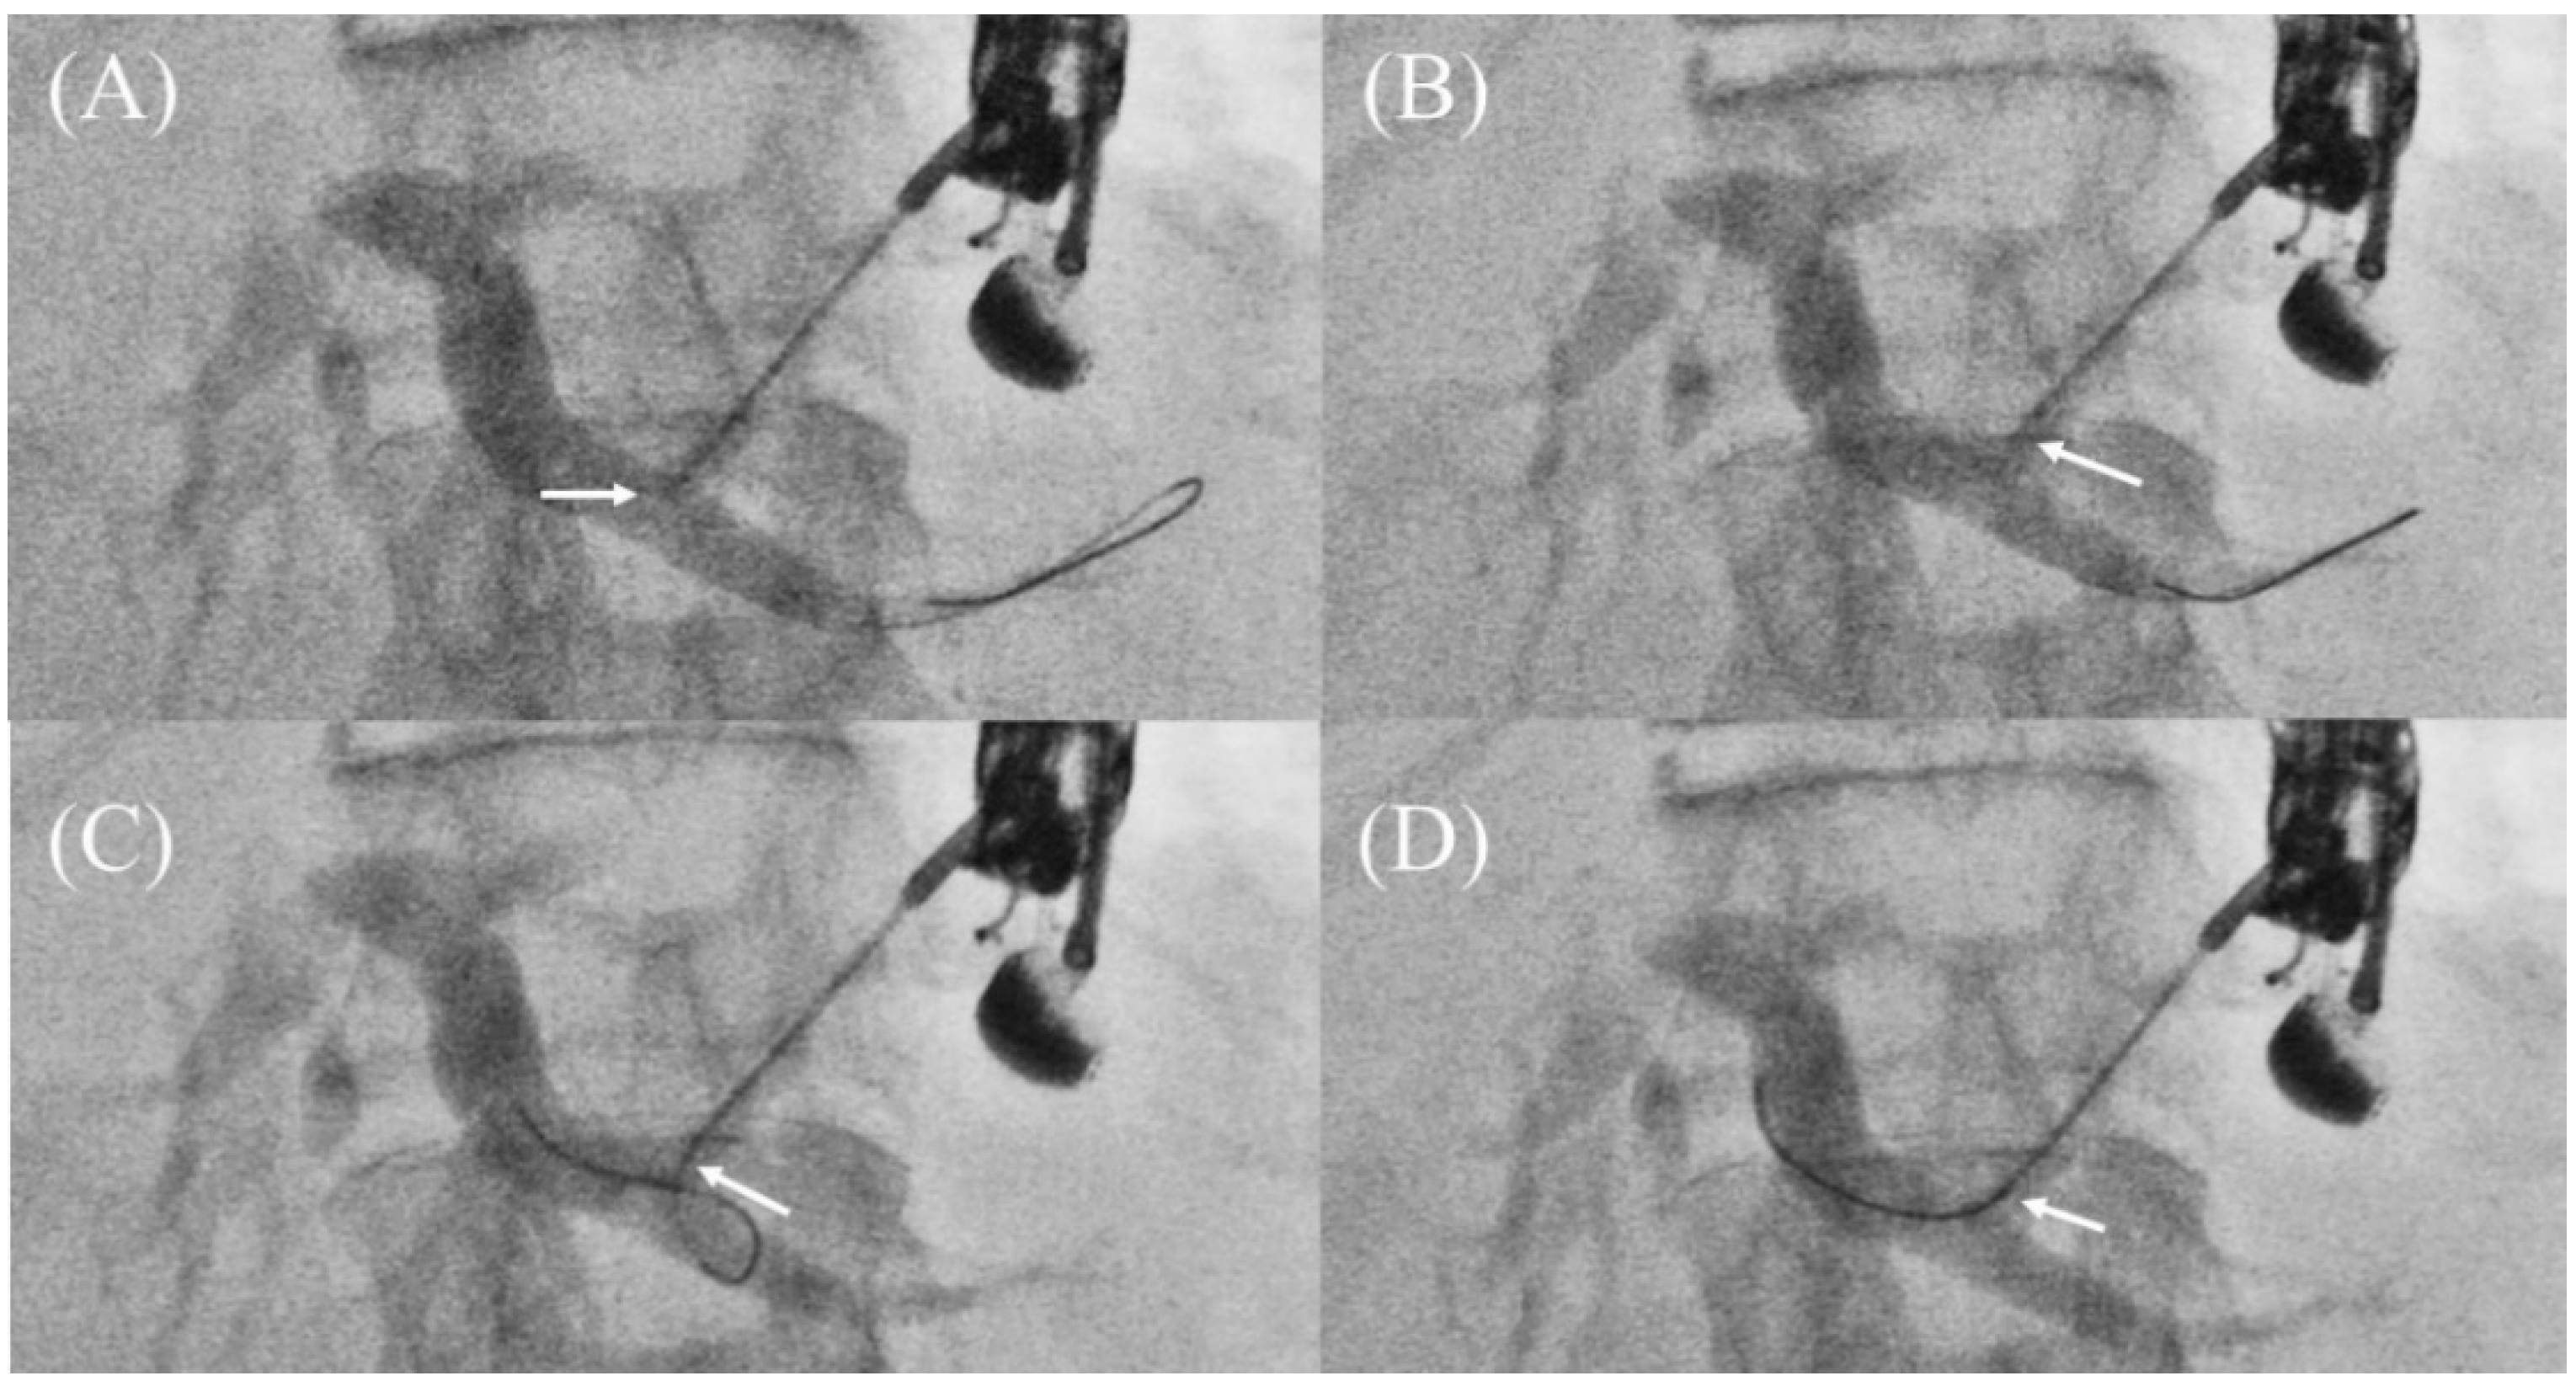

When these methods are unsuccessful, the guidewire must be pulled out and reoriented toward the hilar region. However, if there is any resistance while pulling, the guidewire should not be pulled out forcibly because the tip of the guidewire may be sheared off and remain as a foreign body. In such a case, it is recommended to pull the guidewire out while slowly moving it back and forth with rotation. If this does not work, Ogura et al. reported the usefulness of the “Liver impaction technique” [40]. By pulling the needle tip slightly into the hepatic parenchyma, the angle between the guidewire and the needle is loosened, and the tip of the needle is covered by the hepatic parenchyma to prevent shearing the guidewire (Figure 12A–D). The aforementioned dedicated needle (EchoTip Access Needle; Cook Medical) is expected to prevent shearing of the guidewire [17,32], but is not yet widely available in the world.

Figure 12.

Liver impaction technique for redirection of a guidewire. If a guidewire is unintentionally advanced to the peripheral side (A), pull the needle tip slightly into the hepatic parenchyma (B). The guidewire can be pulled without shearing because the tip of the needle is covered by the hepatic parenchyma (C). The guidewire is successfully manipulated toward hilum (D). Arrows indicate the tip of the needle.